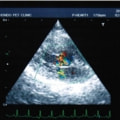

症例6:【ACVIM StageD ビーグル 10歳 去勢雄】

C:超音波 僧帽弁逆流のカラードップラー画像

左側胸壁心尖部領域を最強点とするLevine 5/6の収縮期性心雑音が聴取された。安静時にも咳が認められる。胸部レントゲン検査において重度の心拡大が及び肺水腫が認められた。超音波検査では、重度の僧帽弁閉鎖不全、三尖弁閉鎖不全が認められた。三尖弁逆流速度から肺高血圧症が示唆された。ACE阻害薬、ピモベンダン、硝酸イソソルビド徐放剤、ベラプロストナトリウム、利尿剤としてフロセミド及びスピロノラクトンを用いて治療を行っている。